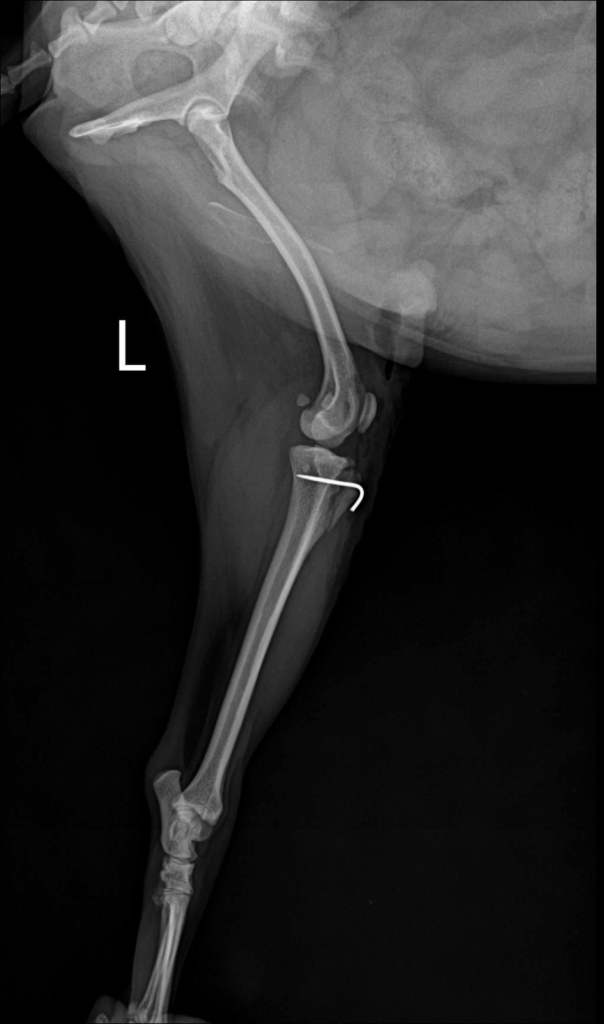

수술 후 엑스레이에서는 슬개골이 정상적으로 대퇴골 고랑 안에 안정적으로 위치한 것이 확인되었습니다.

수술 후 x-ray 사진 / 출처: 미래동물의료센터

수술 후 촬영한 엑스레이에서 수술 전에는 내측으로 벗어나 있던 슬개골이 대퇴골 고랑 안에 정상적으로, 안정적으로 위치해 있는 것이 확인되었습니다.

이는 수술의 구조적 교정이 잘 이루어졌다는 중요한 지표입니다. 환자는 입원 치료를 마친 뒤 무사히 퇴원했고, 현재는 통원 치료와 회복 과정을 안정적으로 이어가고 있습니다.